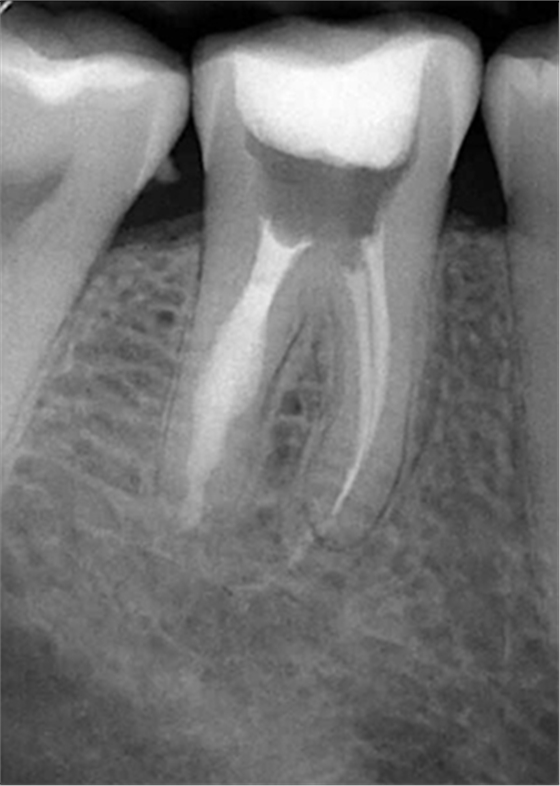

牙內(nèi)吸收通常無明顯癥狀。根據(jù)吸收的類型和原因,主要分為炎癥性吸收和替代性吸收。其中,炎癥性吸收可能繼發(fā)于前期牙本質(zhì)的細(xì)菌感染和創(chuàng)傷,牙本質(zhì)吸收過程的進(jìn)展不伴有吸收區(qū)鄰近部位硬組織的沉積,吸收部位可見大量肉芽組織,典型的影像學(xué)表現(xiàn)為,以根管為中心的橢圓形透光區(qū)。替代性吸收,導(dǎo)致根管內(nèi)牙本質(zhì)缺損的同時,在缺損區(qū)某些部位還伴有骨樣組織的沉積,造成牙髓腔不規(guī)則的擴(kuò)大和根管連續(xù)性的破壞。根據(jù)牙內(nèi)吸收發(fā)生部位和嚴(yán)重程度的不同,又可呈現(xiàn)不同的征象。若吸收部位發(fā)展至牙冠,可以觀察到牙冠上出現(xiàn)粉紅色的點,這是吸收細(xì)胞鄰近的結(jié)締組織高度血管化的結(jié)果。當(dāng)吸收部位位于根方,則可使得根管原有的形態(tài)缺失,X線片可見根管局部氣球樣的膨大,通常邊界清晰。若牙髓還有部分的活力,則患牙可能有慢性牙髓炎的表現(xiàn);若牙髓完全壞死,則可能發(fā)展成根尖周炎,而出現(xiàn)相應(yīng)的癥狀。竇道的出現(xiàn)往往是己發(fā)生慢性根尖膿腫或根管側(cè)穿的表現(xiàn)。由于患牙冠方的牙髓通常己經(jīng)壞死或被去除,因此敏感性測試常為陰性。